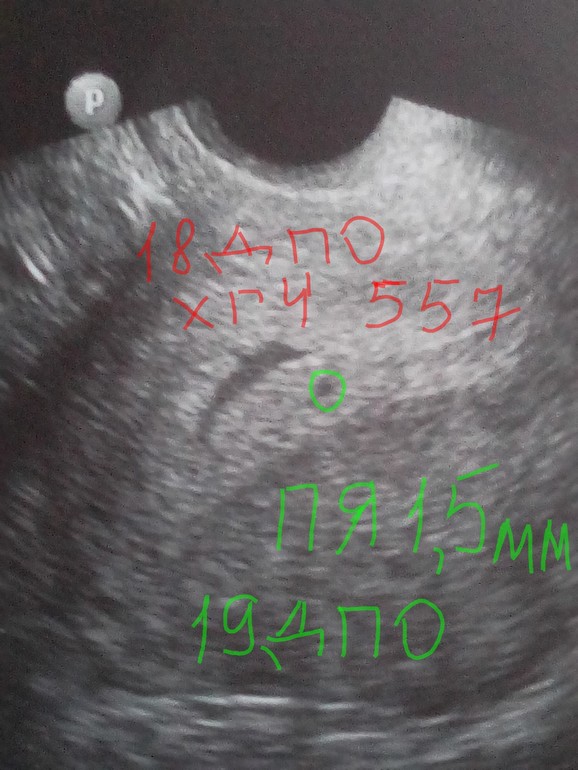

В 5+4( вагинальное):

В 4+4(вагинальное):